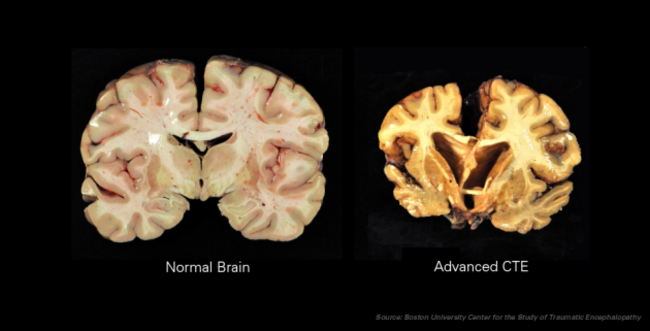

Boston University